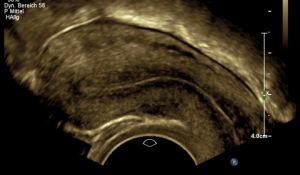

Eileiterschwangerschaft

Mithilfe regelmäßiger Bestimmungen des Schwangerschaftshormons und Ultraschallkontrollen soll hierbei möglichst sicher Klarheit geschaffen werden.

Die korrekte Erkennung einer Eileiterschwangerschaft gelingt unter entsprechender

Überwachung mittels Ultraschall in fast allen Fällen, bevor es zu Symptomen kommt,

so dass eine gute Sicherheit geboten werden kann und eine gezielte, meist operative Therapie im Falle des Nachweises einer Eileiterschwangerschaft eingeleitet werden kann.